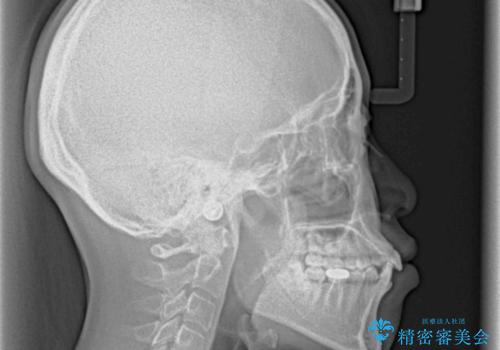

口ゴボが気になる 上下4本の抜歯矯正

- 前歯のデコボコやクロスバイト、口元の突出感を気にして来院された患者様です。

上下左右の第一小臼歯4本を抜歯して、ワイヤー装置にて矯正治療を行うこととしました。

途中出産や育児があり、治療期間長くなってしまいましたが、ストレスなく唇が閉じられるような口元に仕上げることができました。